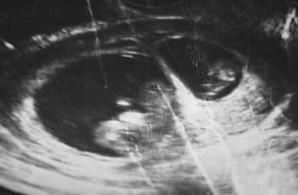

朱麗婭子宮的超音波掃描圖2009年9月25日美國女子朱麗婭·格羅文伯格發現自己懷孕後到醫院進行檢查,醫生髮現她懷上了一個女嬰;可是當朱麗婭兩個禮拜後再次來到醫院接受超音波檢查時,醫生震驚地發現已經懷孕的她“又懷孕”了。據醫學專家稱,這是一種罕見的“異期復孕”現象。

在接受第一次孕檢後兩個禮拜,朱麗婭再次來到當地醫院接受常規孕檢,當醫生再次為朱麗婭進行超音波檢查時,他們被螢幕上的圖像驚呆了。因為超音波圖像顯示,在朱麗婭腹中的胎兒旁,又出現了另一枚更小的胚胎,根據胚胎大小判斷,第二枚胚胎的孕育時間顯然要比第一個胎兒晚上兩周半,這意味著朱麗婭在懷孕期間,竟然又不可思議地再次懷了孕。